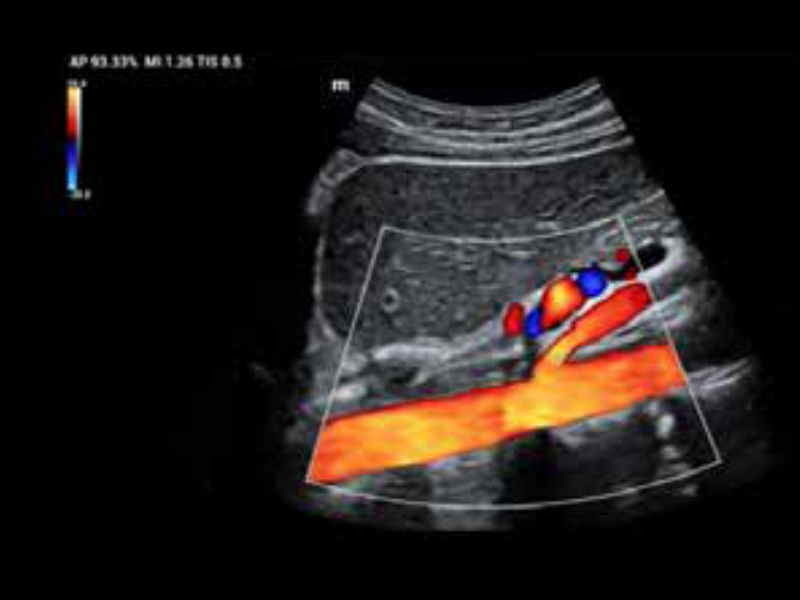

Perfuzja nerek

• zeus-fig5-1-3-uk

Tętniak aorty w trybie dopplera kolorowego

• zeus-fig5-1-4-uk